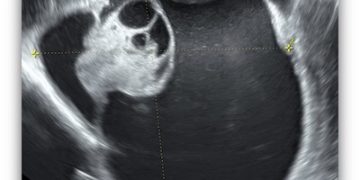

Casi del Mese di Marzo 2023

Cari soci, finalmente online le soluzioni dei casi per il mese di Marzo!!! Grazie a Ilaria Fantasia e Gabriele Saccone!! Caso 1 [pdf-embedder url="https://www.sieog.it/wp-content/uploads/2023/03/caso-clinico-Fantasia-risposta-marzo-2023.pdf" title="caso...